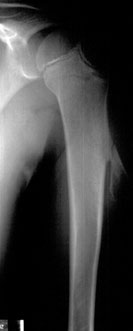

Manuel Z., anni 9, è stato seguito dal suo pediatra per la presenza di una tumefazione nella regione anteriore della spalla sinistra. All’età di 3 anni, infatti, il bambino era stato mandato all’osservazione dello specialista ortopedico per la comparsa della suddetta tumefazione. Essa appariva di consistenza dura, della dimensione di 2 centimetri per 1 e mezzo circa, libera sui piani superficiali ma adesa su quelli profondi; il termotatto non era aumentato, la cute soprastante indenne, i linfonodi nel cavo ascellare non interessati. Il sospetto era stato subito che la tumefazione fosse a provenienza dall’osso ed era stata suggerita l’esecuzione di un radiogramma dell’omero e non di un’ecografia delle parti molli, come poteva sembrare più logco aduna superficiale analisi. Il radiogramma aveva evidenziato la presenza di una esostosi peduncolata del terzo prossimale dell’omero. Poiché tale esostosi era sempre stata del tutto asintomatica, non si poneva l’indicazione chirurgica. Da un accurato esame clinico di tutto il corpo tale esostosi risultava isolata e non facente parte di una malattia esostosante. Alla madre venne consigliato, quindi, di portare il bambino a controllo una volta all’anno per una valutazione clinica dell’estensione delle dimensioni dell’esostosi e dell’eventuale comparsa di sintomatologia algica. Nei controlli periodici che si susseguirono negli anni l’esostosi risultò invariata. All’ultimo controllo, risalente a un mese fa, essa risultava lievemente ingrandita, diventando visibile ad occhio nudo, ed iniziava a dare al bambino la sensazione di averla: venne posta così l’indicazione chirurgica. Si scelse di asportarla durante le vacanze scolastiche, evitando al bambino di perdere due giorni di scuola. Due settimane prima della data prevista dell’intervento, in seguito a un trauma ricevuto nel corso di una partita di pallacanestro a scuola, il bambino accusò un fortissimo dolore al braccio sinistro.

Portato al Pronto Soccorso, eseguiva un radiogramma del braccio che evidenziava la rottura dell’esostosi a livello del suo peduncolo d’impianto. L’esostosi fu asportata il giorno seguente.